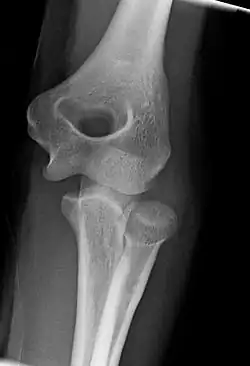

Normal radiograph; right picture of the straightened arm shows the carrying angle of the elbow

When the arm is extended, with the palm facing forward or up, the bones of the upper arm (humerus) and forearm (radius and ulna) are not perfectly aligned. The deviation from a straight line occurs in the direction of the thumb, and is referred to as the "carrying angle".[22]

The carrying angle permits the arm to be swung without contacting the hips. Women on average have smaller shoulders and wider hips than men, which tends to produce a larger carrying angle (i.e., larger deviation from a straight line than that in men). There is, however, extensive overlap in the carrying angle between individual men and women, and a sex-bias has not been consistently observed in scientific studies.[23]